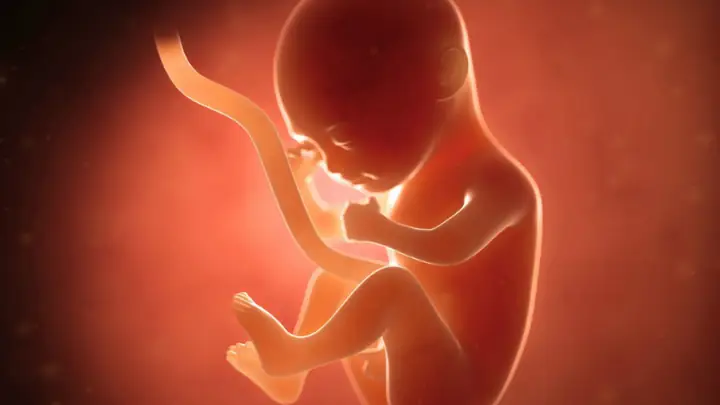

- Tuần 7-8: Các cơ quan chính đã hình thành, phôi thai bắt đầu có hình dạng giống con người.

Tuần 9-12

- Tuần 9: Phôi thai chuyển sang giai đoạn thai nhi.

- Tuần 10-12: Các cơ quan tiếp tục phát triển, thai nhi có thể cử động nhẹ.